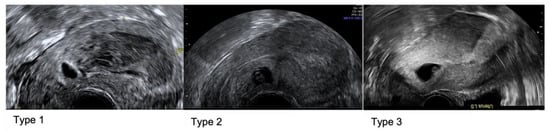

- Jordans, I.P.M.; Verberkt, C.; De Leeuw, R.A.; Bilardo, C.M.; Van Den Bosch, T.; Bourne, T.; Brolmann, H.A.M.; Dueholm, M.; Hehenkamp, W.J.K.; Jastrow, N.; et al. Definition and sonographic reporting system for Cesarean scar pregnancy in early gestation: Modified Delphi method. Ultrasound Obstet. Gynecol. 2022, 59, 437–449. [Google Scholar] [CrossRef] [PubMed]